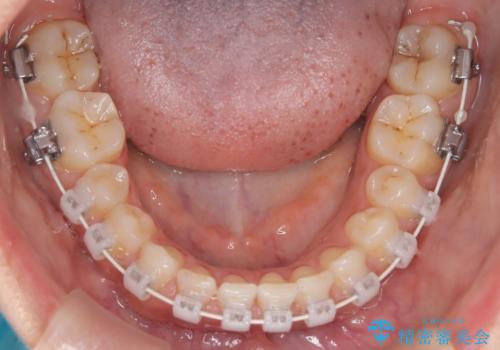

本症例では、非抜歯での治療を選択したため、スペースを確保するためにIPR(歯間削合)を行い、歯列を整えました。オーバージェット(上の前歯と下の前歯の水平的なズレ)は残る結果となりましたが、見た目や機能の改善を重視し、患者様と治療計画を共有しながら進めました。治療中は、歯列全体のバランスと噛み合わせを考慮しつつ、矯正装置の適切な使用を徹底しました。当初の計画通りに治療を完了し、患者様にも満足していただけました。